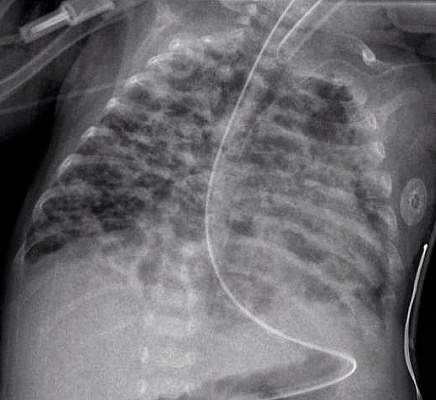

Бронхолегочная дисплазия – самое частое

хроническое заболевание легких у недоношенных новорожденных детей с критично

низкой массой тела (до 1 кг при рождении). Оно связано с незрелостью легочных

тканей, токсичным воздействием кислорода при искусственной вентиляции легких и

рядом других факторов. В настоящее время выделяют легкую, среднюю и тяжелую

степени болезни. Первоначальная задача врачей – подобрать лечение, которое

снизит риск развития серьезных форм недуга.